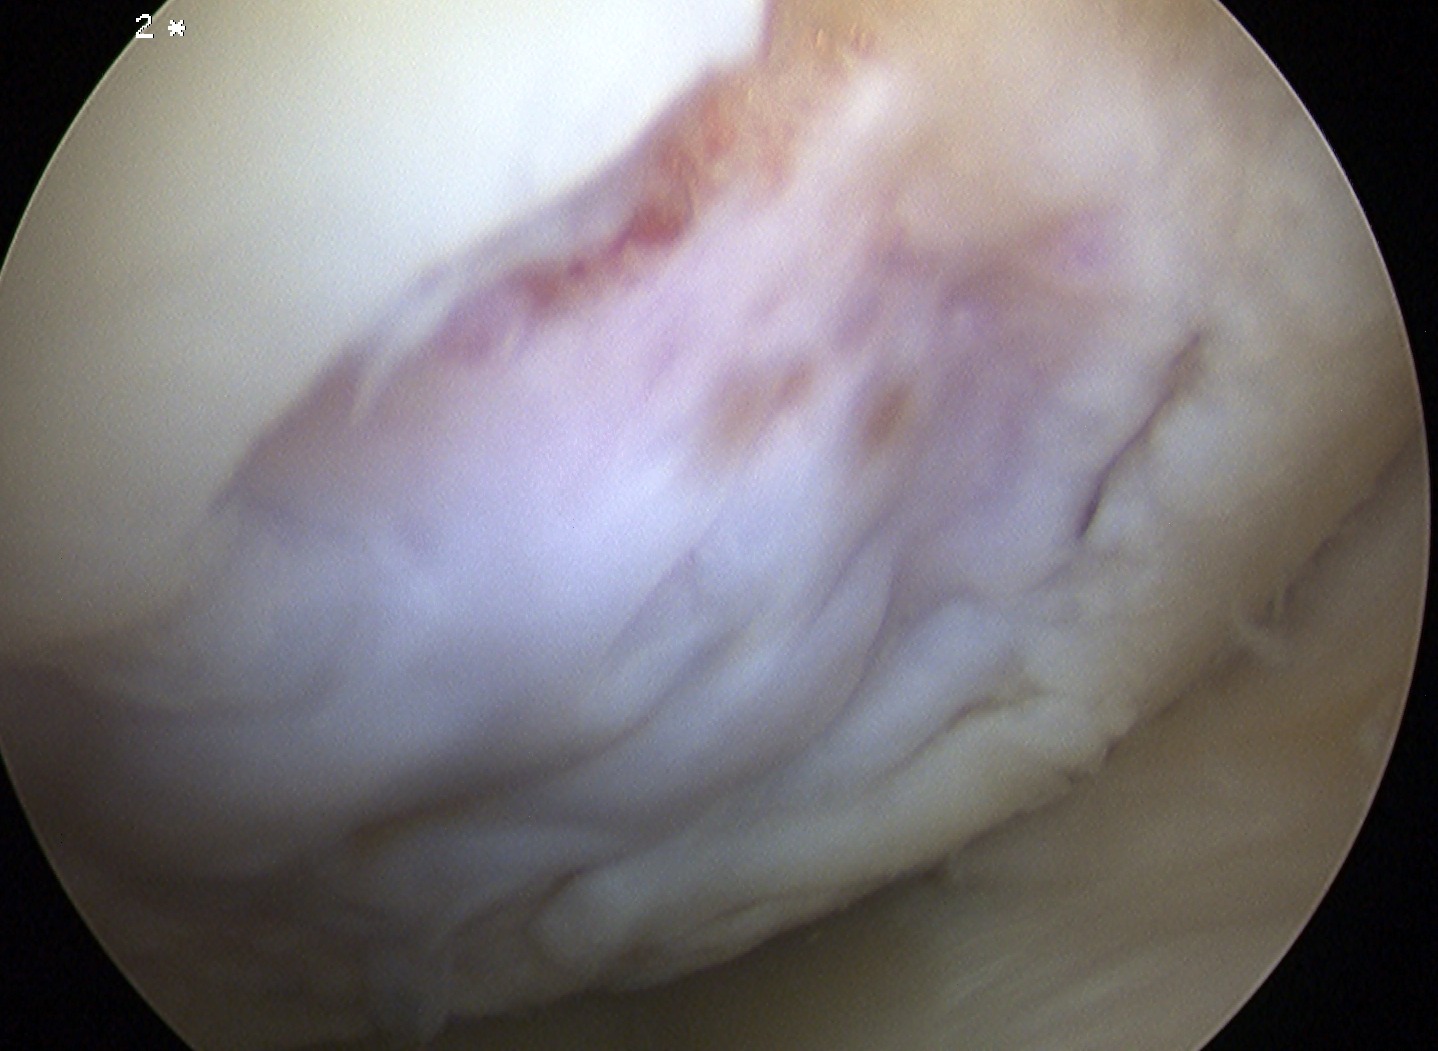

ICRS Arthroscopic Classification

1. Cartilage Intact

2. Partial discontinuity but stable on probing

3. Completely detached but insitu

4. Fully detached with crater & loose body

A. Chondral Fragment Salvageable

- recent

B. Chondral fragment unsalvageable

- increased in size / change in shape